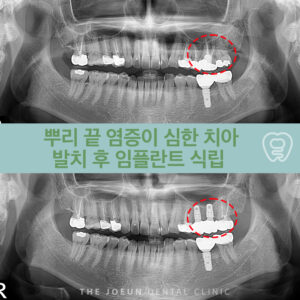

달서구임플란트잘하는곳 치조정 접근법을 통한 상악동 뼈이식술 임플란트는 치아가 빠진 부위에 티타늄으로 만들어진 인공치근을 치조골에 식립하여 상부에는 크라운을 제적하여 연결하는 보철치료르 말합니다. 치아의 뿌리부터 머리까지 자연치와 비슷한 모양으로 심미성이 뛰어나고, 자연치와 유사한 기능을 보이는데요. 이는 잇몸뼈에 식립체를 직접 식립하게 되는데 진행을 위해서는 치조골의 양과 상태가 충분해야 합니다. 치아를 상실했어도 치조골 상태가 더보기…